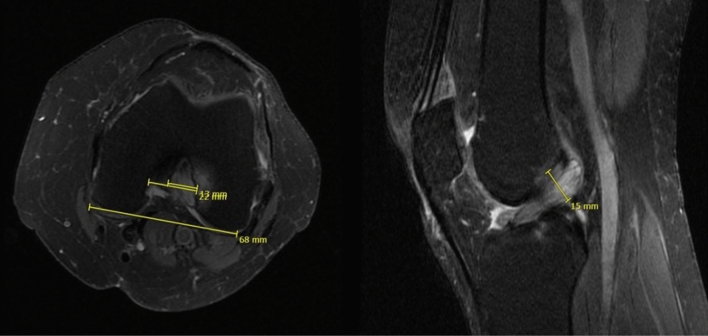

MRI evaluation was conducted with the INFINITT Healthcare PACS viewing software (Frankfurt am Main, Germany). Analysis included measurement of the thickness of the ACL (largest diameter on sagittal fat-saturated (fs) proton-density-weighted turbo spin-echo (PDw TSE) sequences), ratio of ACL (largest diameter of the ACL on axial PDw TSE) and intercondylar width, signal intensity of the ACL and presence of bone edema or intraosseous cysts (Fig. 2). MRI analyses were performed before and after surgery at final follow-up. Postoperative MRIs were available from all patients with complete resection of the ACL and from 7 patients who underwent partial resection of the ACL.

Fig. 2.

Measurement in the MRI of the MDACL: ratio of the ACL and intercondylar notch width on the axial view and ACL thickness on the sagittal view